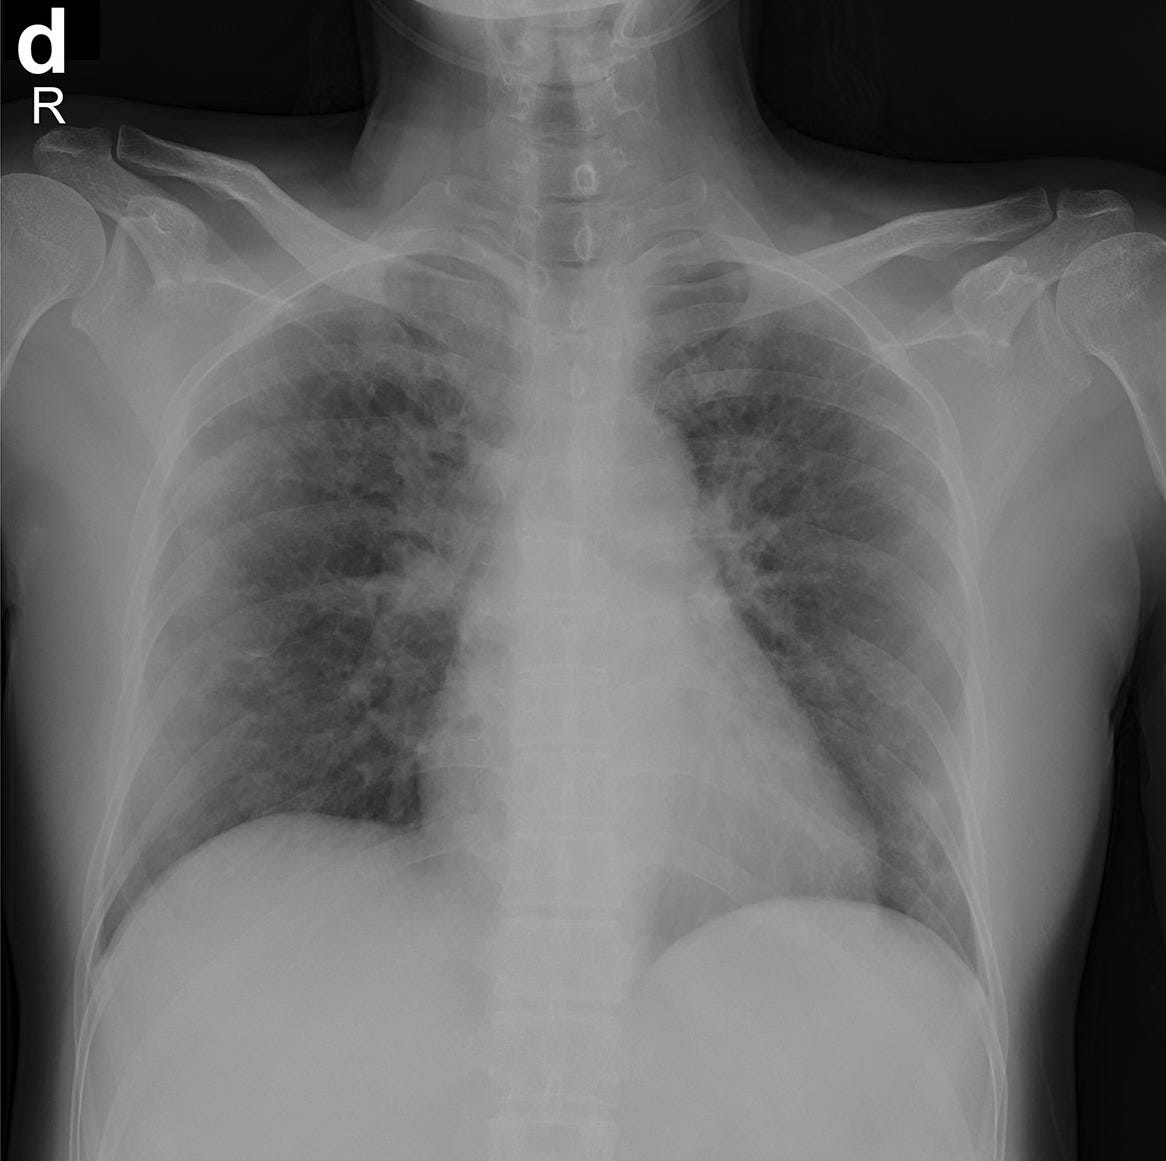

In our experience, baseline cxr had a sensitivity of 68.1%. It is mentioned that this dataset is continuously updated. The dataset is provided along with the tool so that researchers, or anyone who wants to play, can explore and modify it.

This dataset contains 3 types of images: This other repository in kaggle we have also taken into account: The proposed approach selected successfully 130 and 86.